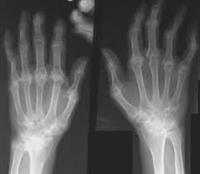

2. الأشعة السينية

تعمل الأشعة السينية بشكل أفضل عند الأطفال الذين تزيد أعمارهم عن 4 - 6 أشهر، حيث في ذلك العمر تكون تكونت عظامهم بما يكفي لرؤيتها بالأشعة السينية.